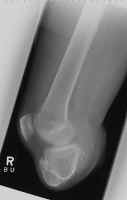

These images demonstrate a BKA that is too short to allow for use of a prosthesis.